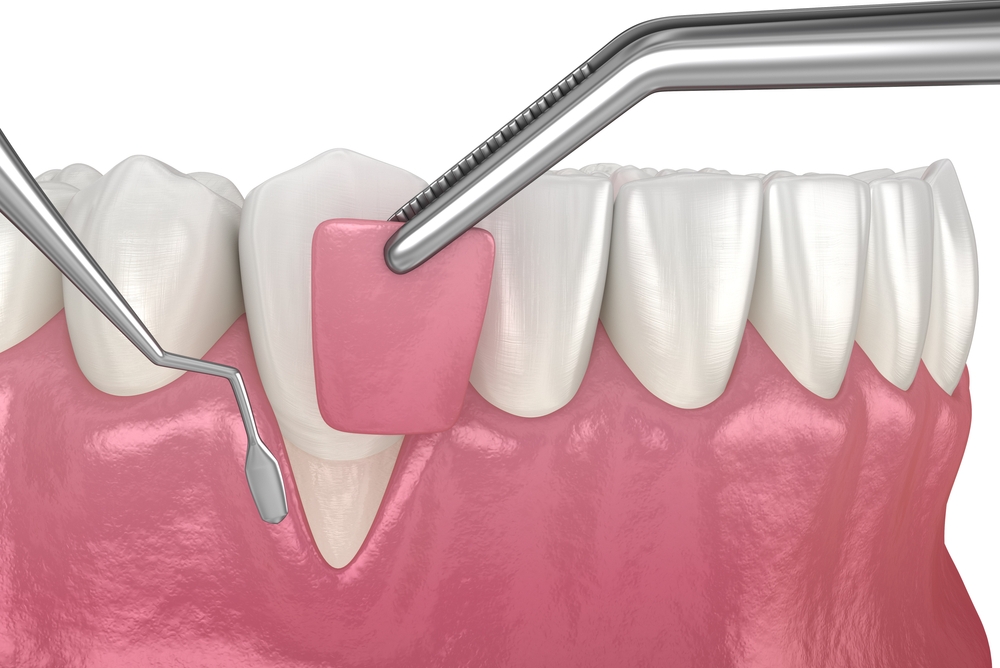

Paradentosebehandling

Læs mere